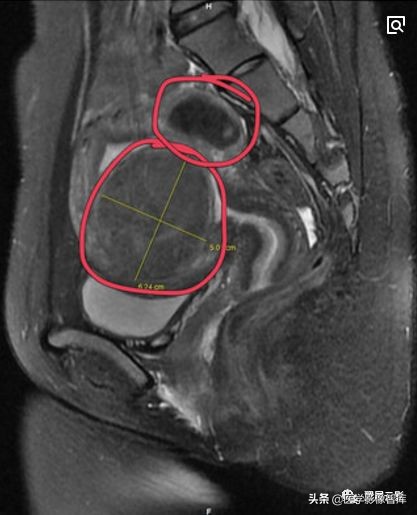

卵巢囊腺瘤

本病分为浆液性囊腺瘤和黏液性囊腺瘤,约占卵巢原发肿瘤的1/4,双侧发生率约为15%,浆液性囊腺瘤和黏液性囊腺瘤可以并存,浆液性囊腺瘤呈单房或多房改变,黏液性囊腺瘤多为多房改变,好发年龄为20—50岁,临床症状有腹部不适或隐痛,腹部包块等,少数伴有月经紊乱,浆液性囊腺瘤患者有时可出现腹水,病理表现:肿瘤切面为单房或多房性,囊壁光滑或有乳头状突起,浆液性囊腺瘤囊壁上皮为单层立方或矮柱状上皮;黏液性囊腺瘤囊壁上皮为单层黏液柱状上皮。

右侧卵巢粘液性囊腺瘤

注意观察描述卵巢囊腺瘤的大小及均匀液性长T1,长T2信号特点,同时应观察描述囊腺瘤的分隔和乳头状壁结节,一般在T2WI上显示清晰,黏液性囊腺瘤内有粘蛋白,T1WI呈等或略高信号,T2WI为高信号,此点可与浆液性囊腺瘤相鉴别。